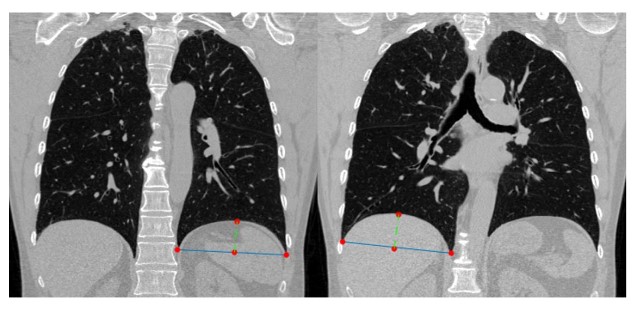

Abstract Background Dynamic hyperinflation is central to dyspnoea, exercise limitation, and exacerbations in chronic obstructive pulmonary disease (COPD). While studied previously in moderate-severe COPD, the relevance of diaphragm dome height on clinically important outcomes has been under-investigated in mild-to-moderate COPD. Methods Canadian Cohort Obstructive Lung Disease participants with spirometry-confirmed COPD, symptom-limited incremental cardiopulmonary exercise testing, and computed tomography image data were included. Base-to-apex left and right diaphragm dome height (DDH) was automatically segmented, with increased height implying less flattening and thus less hyperinflation. Dynamic hyperinflation was defined as ?150?mL reduction in inspiratory capacity (IC) from rest to peak-exercise. Cross-sectional linear regression models were fitted between left and right DDH (predictor variables) with peak IC (ICpeak), peak workload (Wpeak), FEV1, and CAT score (outcome variables), and in longitudinal (Anderson-Gill) models with “symptom-based” and “event-based” exacerbations. Results are reported as parameter estimates or hazard ratios with 95%CIs per interquartile range dome height increment. Results Among 304 participants (mean age 64.7±10.3, 41.8% female, 44.4% with mild COPD), each left and right DDH increment, respectively, was associated with ICpeak (0.21[0.13,0.29]L, 0.13[0.07,0.19]L), Wpeak (9.54[5.03,14.04]W, 6.04[2.45,9.62]W), FEV1 (0.17[0.10,0.25]L, 0.08[0.02,0.14]L), and CAT score (?1.36[?2.39,?0.33], ?0.82[?1.63,0.00]). Left DDH alone was associated with both symptom-based (HR: 0.82[0.74,0.91]) and event-based (0.83[0.73,0.95]) exacerbations. Of 167/304 participants with confirmed dynamic hyperinflation (?IC=?0.47±0.25?L), left DDH alone was associated with all outcomes (ICpeak, Wpeak, FEV1, CAT, and symptom-based/event-based exacerbations). Conclusions Left DDH appears to be a clinically important marker for operational lung volume changes, lung function, exercise performance, disease burden, and exacerbations in mild-to-moderate COPD.